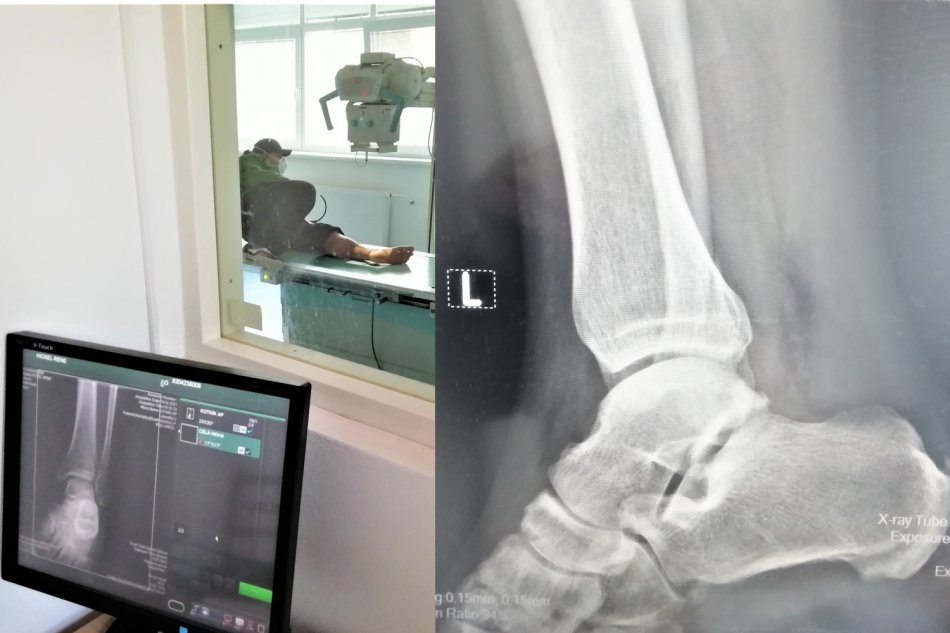

Galéria k článku Na röntgenológii v Moravciach sa nenudili: Vlani zrealizovali 10-tisíc vyšetrení

Zdroj: AGEL SK